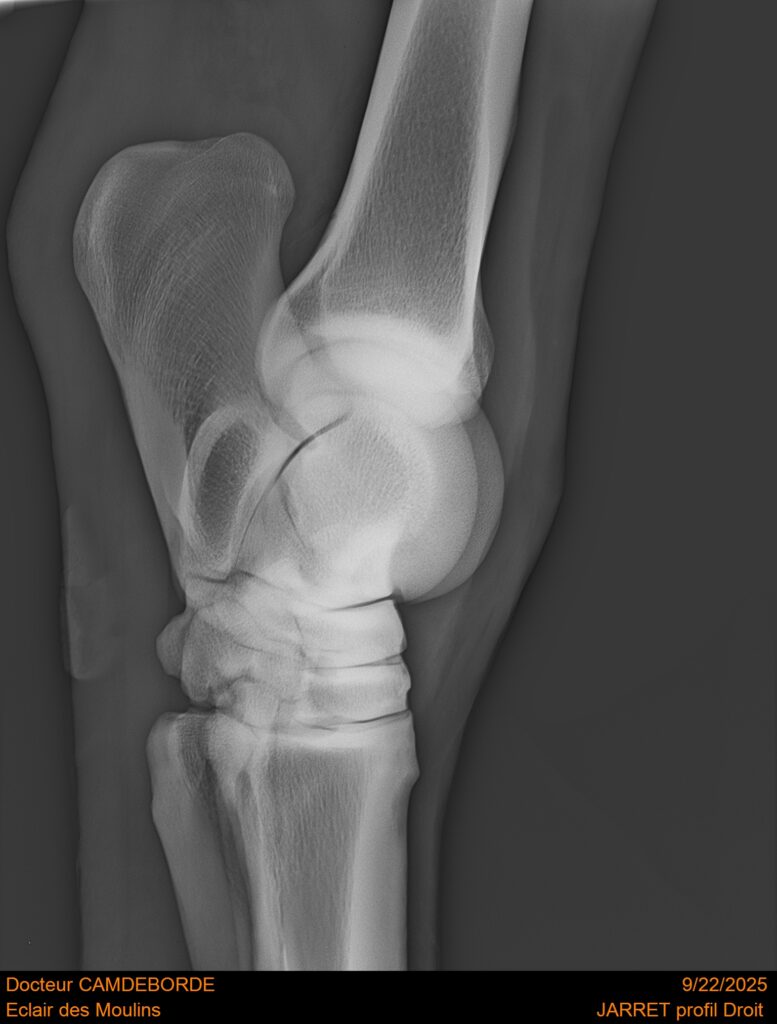

10 K ✨ TOP cheval pour épreuve Amateur ! ECLAIR DES MOULINS, selle Français de 11 ans. Classé sur 1m05. Idéal pour aller faire jusqu’à 110 voir 115, cheval pas usé (une vingtaines de parcours). Très gentil au quotidien, cheval de famille. Courageux et respectueux à l’obstacle. Bien dressé, change de pieds. Bilan pieds, boulets, jarrets, grassets et visite clinique effectuée cette semaine. il peut vivre au box comme au champs, cheval rustique. toise environ 1m60 porteur. Pour le compte de son propriétaire car manque de temps.

RADIOS ET CLINIQUE